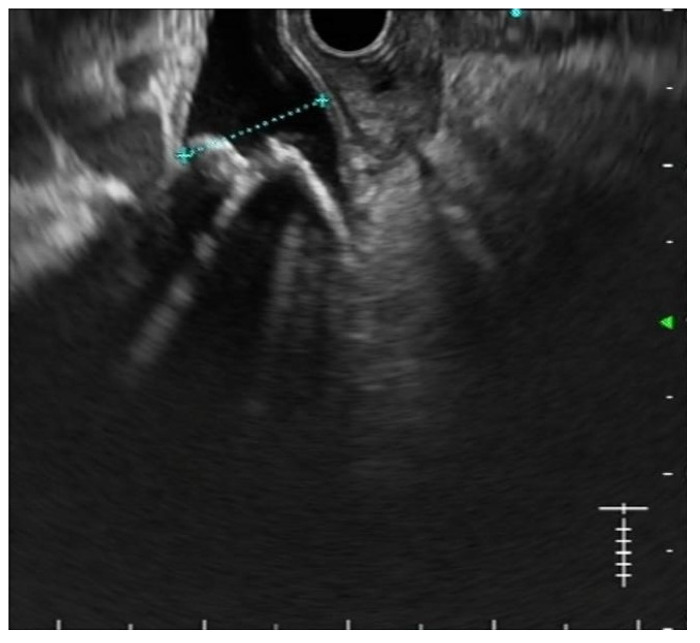

Secondly, the excellent diagnostic accuracy of EUS for CBD stones, together with its findings regarding stone number and size, is often useful in planning the best treatment strategy [ref. 20] Figure 1. In particular, performing EUS before ERCP allows predicting the expected grade of complexity of the ERCP procedure [ref. 21]. As a result, physicians may plan in advance the execution of ancillary techniques such as large balloon dilation, electrohydraulic or laser lithotripsy, cholangioscopy, and even referral to other institutions in order to improve the success rates while keeping the adverse events as low as possible [ref. 22].